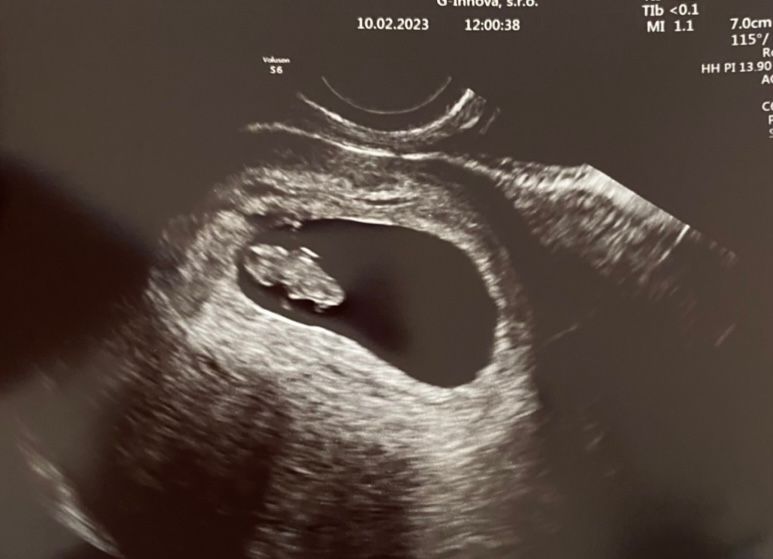

Pasernes, хм🤔7,5? я была недавно у врача на сроке 7 недель 3 дня, вот результат: Изображение А вам не порекомендовали утрожестан хотя бы? я бы на вашем месте сходила еще в другую клинику на узи, на недельку постельный решим + утрожестан и метилфолат.. удачи ☘️

Добавлю: 21 января - хгч 2115 Прием на узи и фото выше: 10 февраля! мне кажется, вам надо ориентироваться не на срок, а на ваш хгч. Срок вас пугает